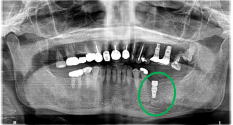

女性Nさん 60代(インプラント)

主訴

左下、歯がないところに歯を入れたい。

治療内容

3本歯がないところに、インプラントを2本埋入しました。

所感

2022年5月に上前歯に2本、2023年12月に右下に2本、インプラント治療をしていましたので、今回も左下3本欠損のところに義歯ではなくインプラントを選択されました。今回も X-Guideを使った埋入で、安心安全に行うことできました。

インプラント2本:¥363,000×2本=¥726,000(税込)

ポンティック1本:¥115,500(税込)

合計:¥841,500(税込)

Before

After